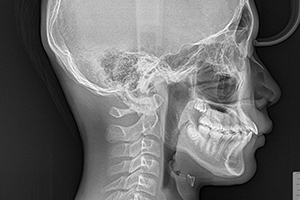

小児マウスピース矯正のマルチファミリーは早期の段階で永久歯の歯並びや、かみ合わせを正しくしたい方におすすめです。一般的な矯正治療では金属ワイヤー、ブラケットを使用して矯正を行いますが、マルチファミリーの小児マウスピース矯正では、寝ている間と日中に1時間以上装着して歯や歯茎に優しい力で歯並びを整えていこうという目的の器具です。全部で5シリーズの装置があり、使用目的や適応年齢によって幅広くお選びいただくことが可能です。